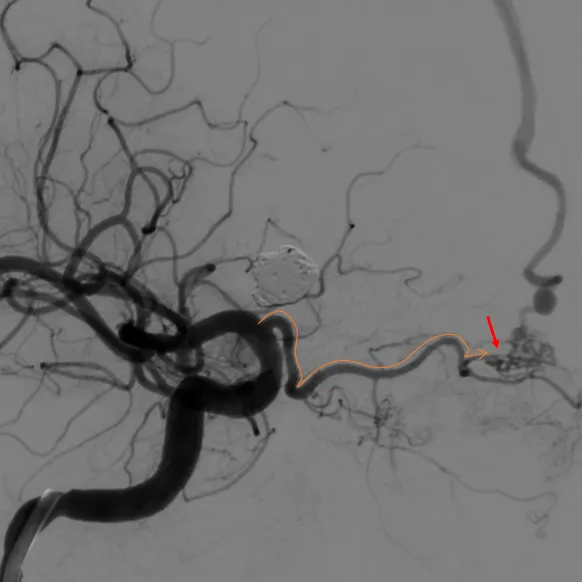

术前造影

左颈总造影,未见异常供血

右颈外造影,可见右侧蝶腭动脉分支供血,但无良好路径显示

右颈内造影,可见右侧眼动脉-筛后动脉供血,见经额底静脉-双侧额部皮层静脉向上矢状窦方向引流

经右眼动脉工作路径

SONIC微导管到位后,手推造影确认

SONIC微导管造影证实